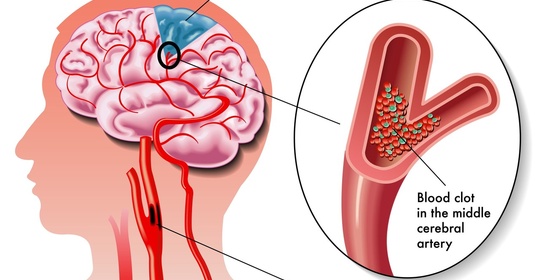

短暫性腦缺血發作的診斷與治療方法